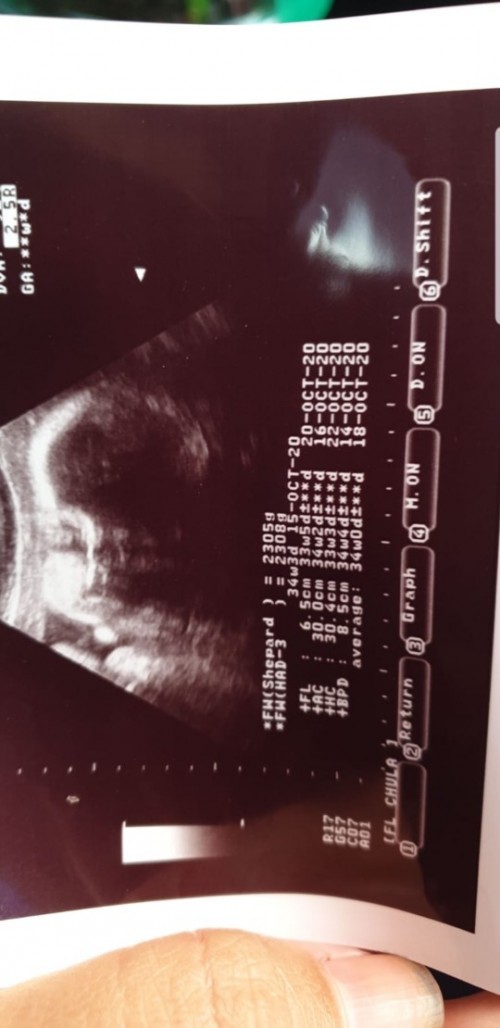

ซาวด์ตอน 26 สัปดาห์ กำหนดคลอดต้นเดือนพฤศจิกาค่าาา

ซาวด์วันที่9 กย.63 ลูกชายค่ะ 32W3D

ซาวตอน18วีค ตอนนี้จะ29วีคคะ